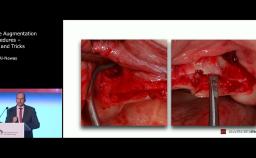

Stephen Chen discusses the challenges that surgeons face when looking at dental implant solutions for the rehabilitation of patients with extended edentulous spaces in the anterior maxilla. He covers anatomical and surgical considerations both from a theoretical and practical point of view, using a clinical case to illustrate the topic.

This lecture is accompanied by two more lectures covering the restorative considerations and the technical considerations when looking at the expanded edentulous space in the anterior maxilla. The series highlights the necessity of communication and teamwork among the involved specialists to be successful with their treatment of the case.